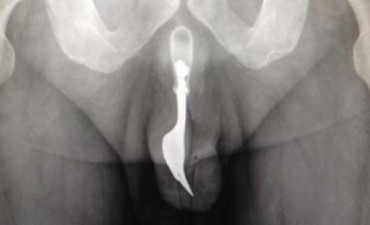

El sangriento hecho ocurrió en Oxford, Inglaterra. Un joven de 21 años, obsesionado con el personaje de historietas, apuñaló a su padrastro, madre y hermana, y se quitó la vida. Solía subir imágenes a Internet caracterizado como el "Hombre X", con cuchillos como garras.